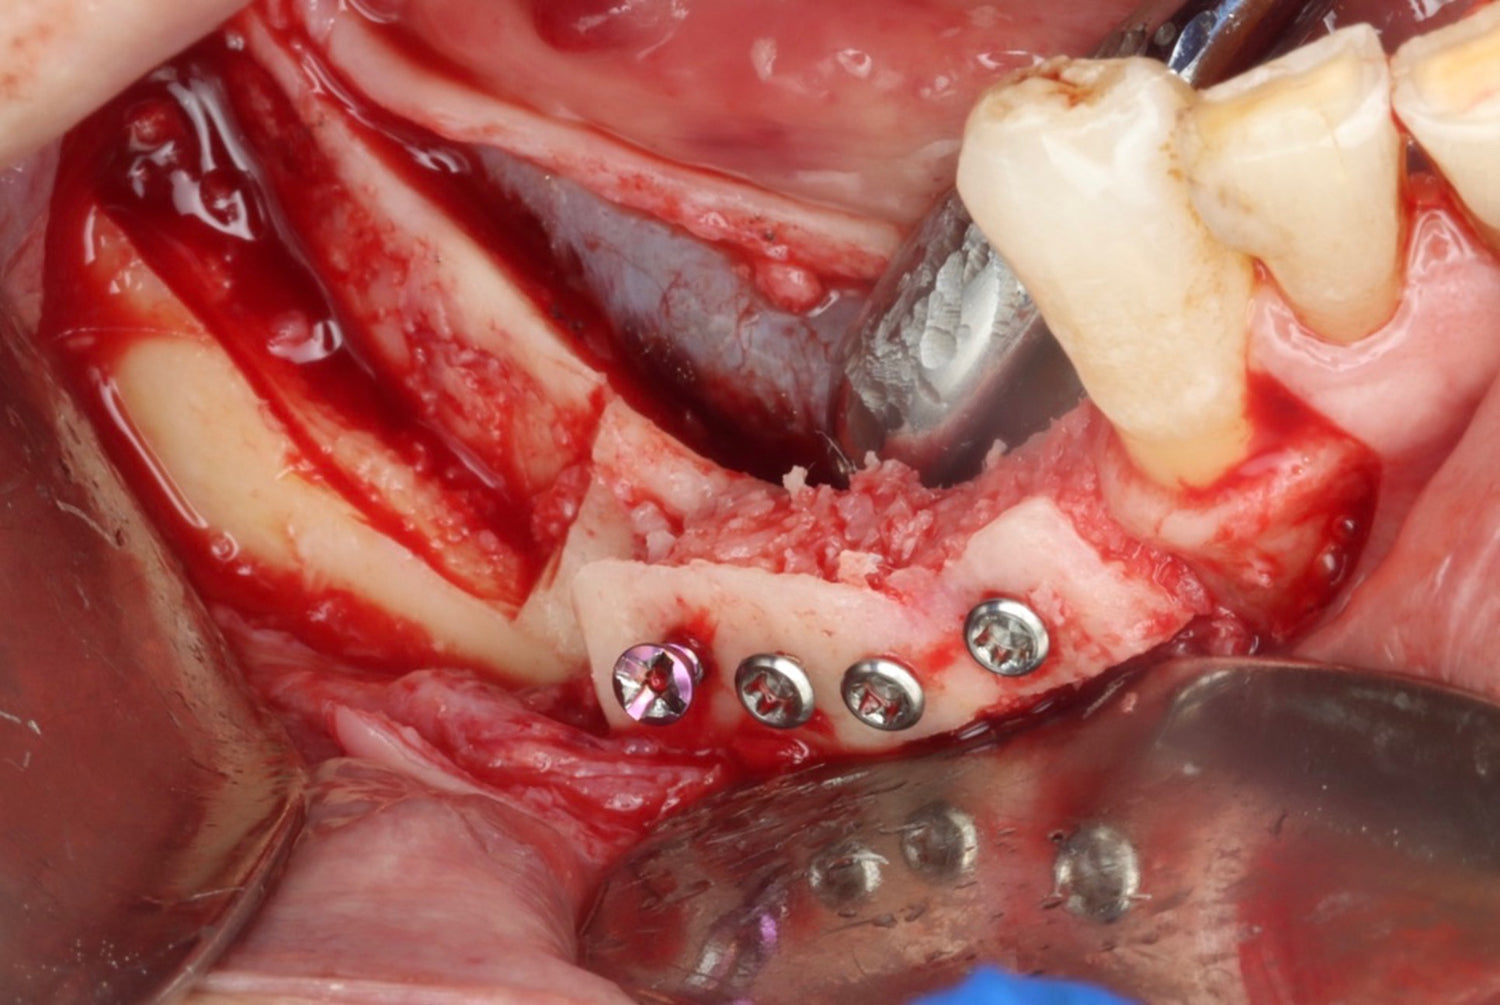

- Learn advanced bone augmentation techniques using autogenous bone plates, from principles to implementation

- Khoury plate